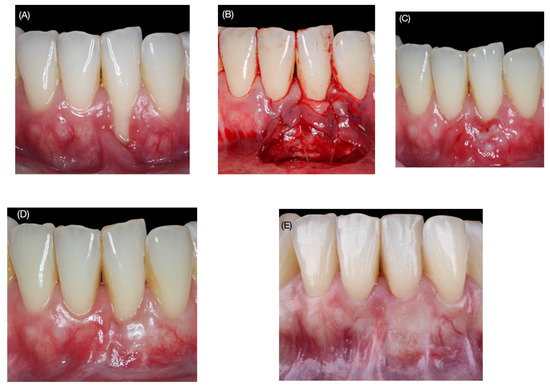

Clinical Outcomes of the Double Lateral Sliding Bridge Flap Technique with Simultaneous Connective Tissue Graft in Sextant V Recessions: Three-Year Follow-Up Study

2.1. Surgical Protocol